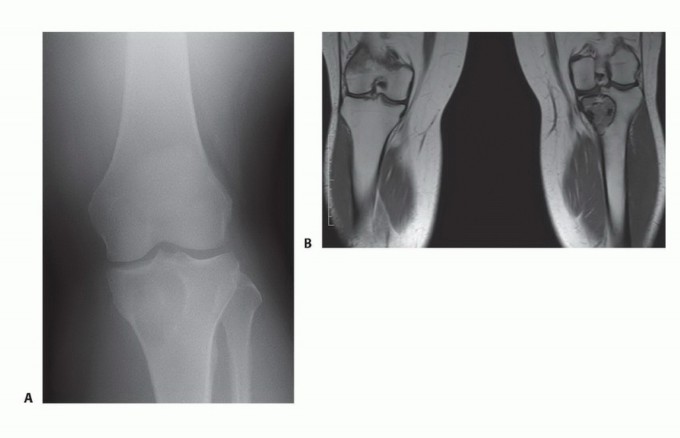

- التقييم الشامل: يقوم الدكتور هطيف بإجراء تقييم سريري دقيق، ومراجعة التاريخ المرضي للمريض، وإجراء الفحوصات التصويرية اللازمة (الأشعة السينية، الرنين المغناطيسي، الأشعة المقطعية، ومسح العظام) لتحديد حجم الورم وموقعه وعلاقته بالهياكل الحيوية المحيطة.

- الخزعة (Biopsy): في معظم الحالات، يتم أخذ خزعة من الورم لتأكيد التشخيص النسيجي وتحديد ما إذا كان حميدًا أو خبيثًا.